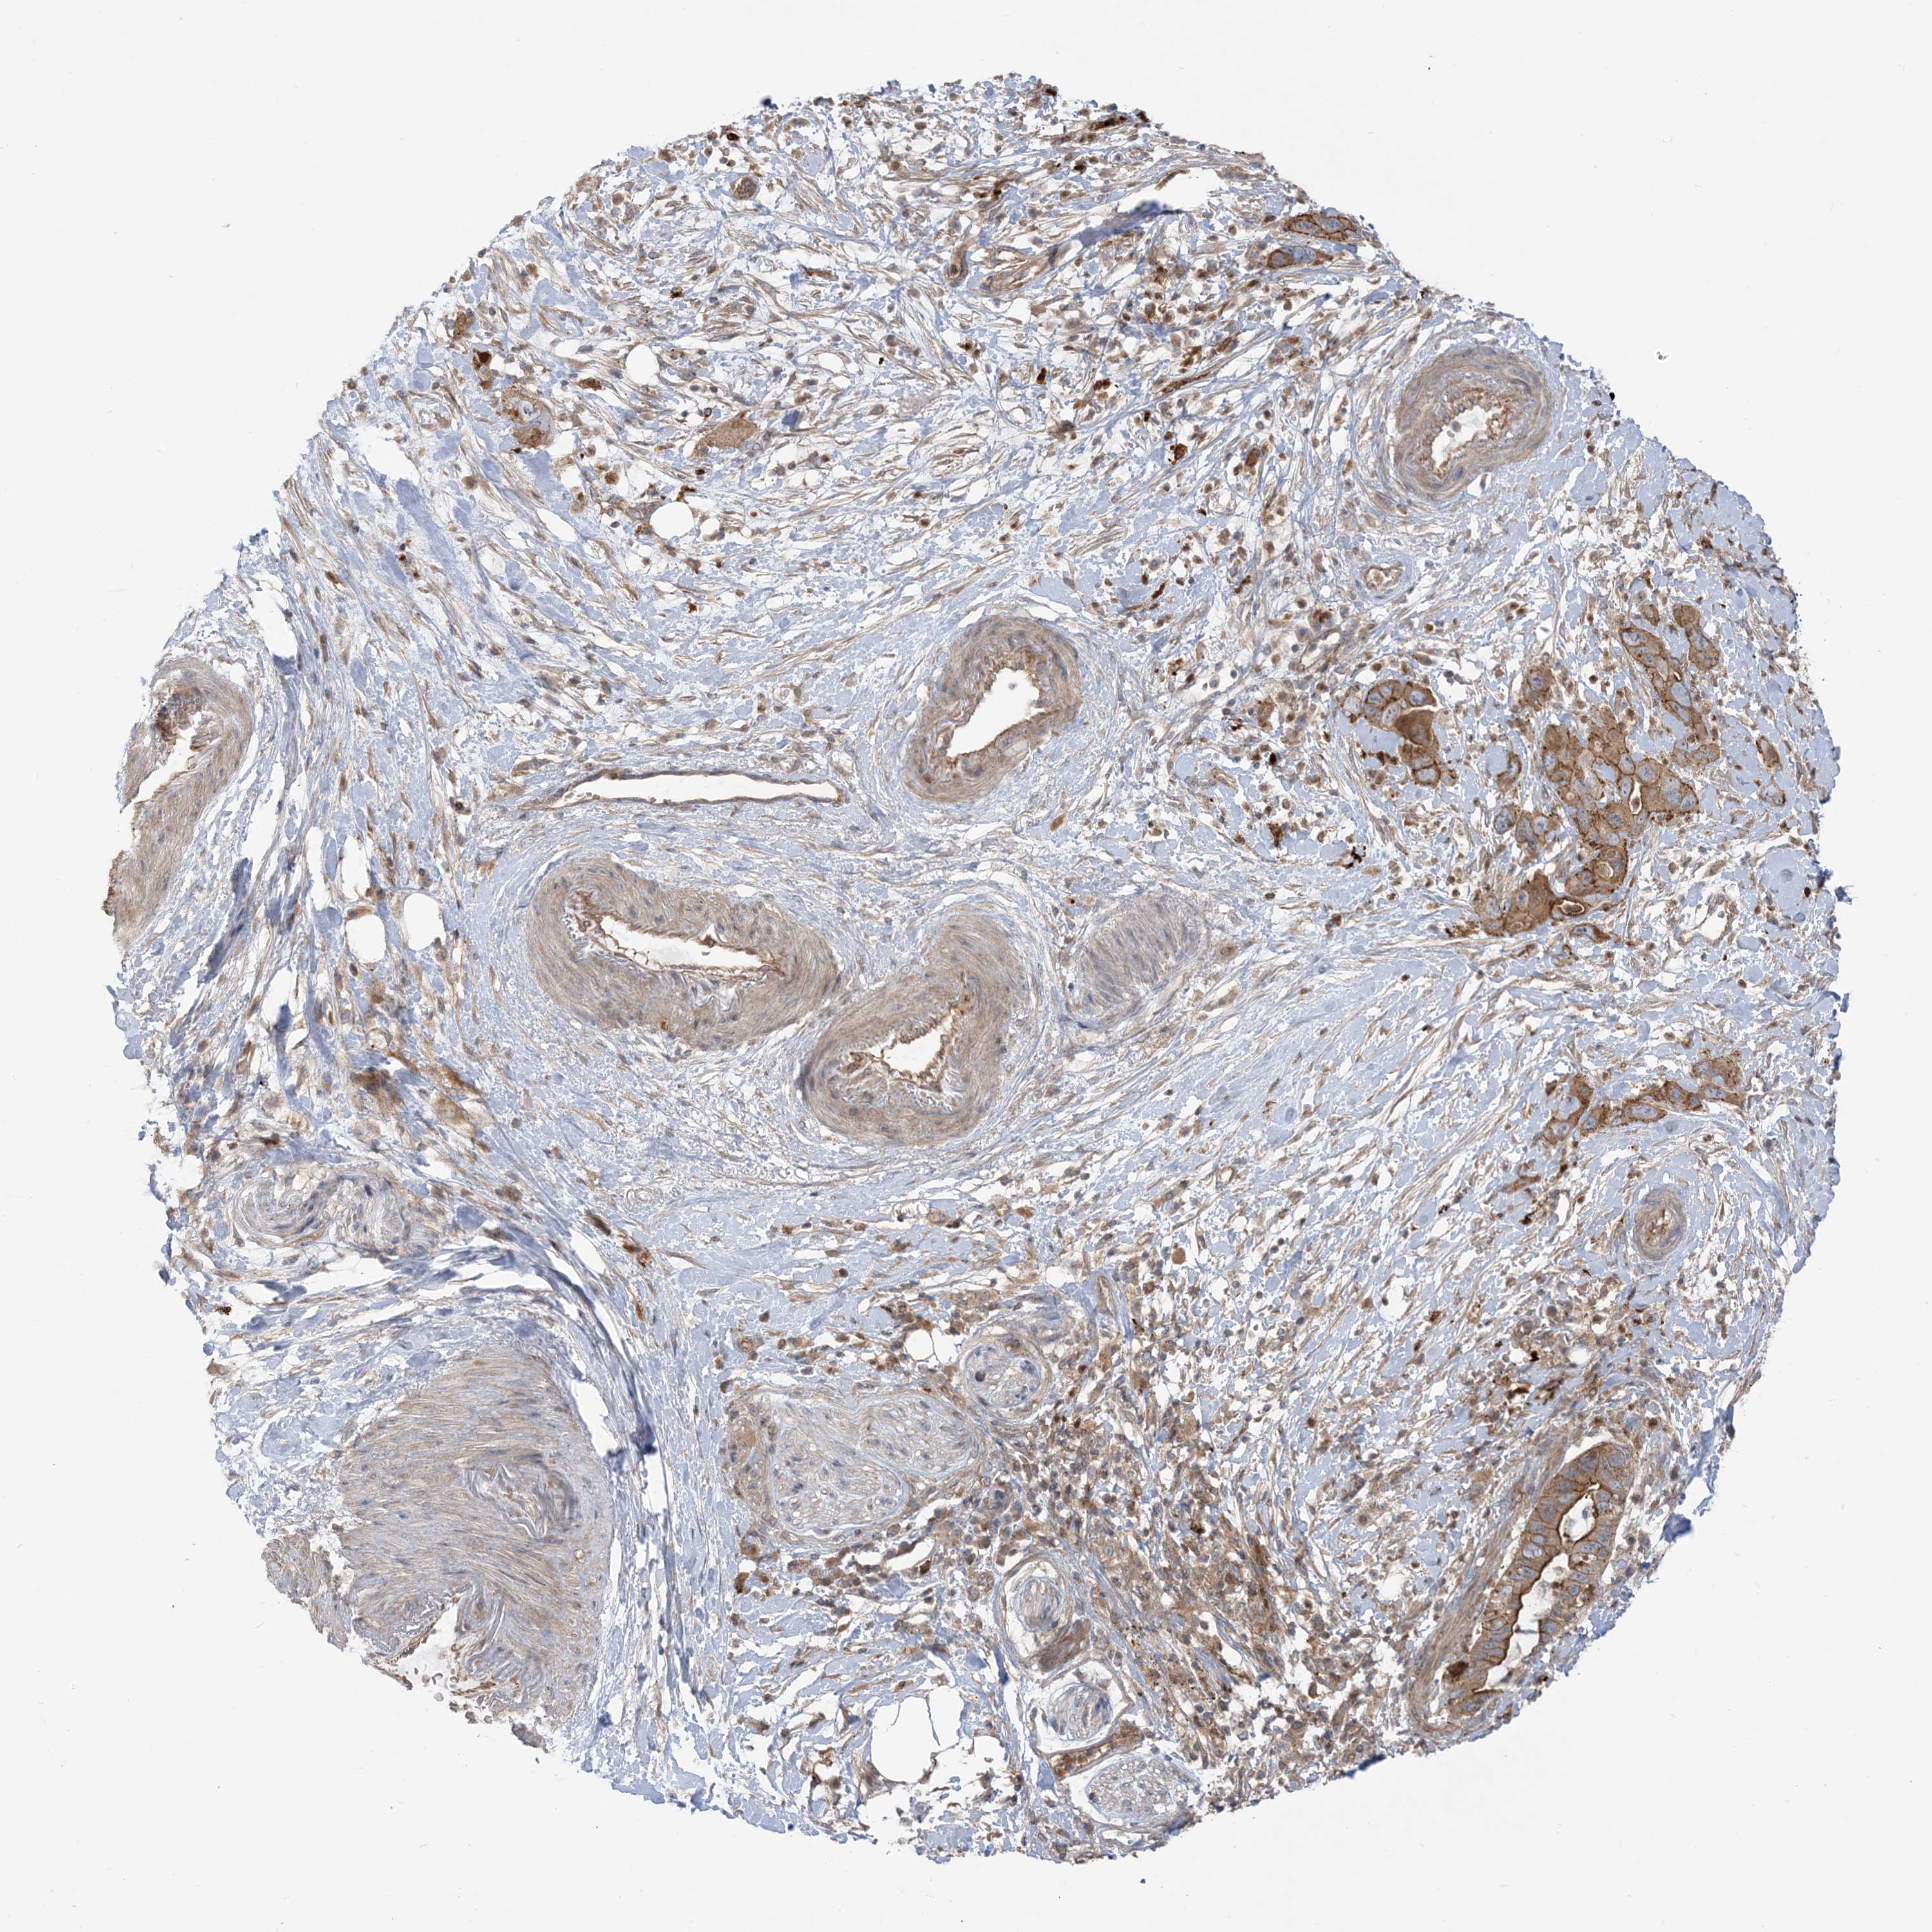

PANCREATIC CANCER - Protein expressioni

A mouse-over function shows sample information and annotation data. Click on an image to view it in a full screen mode. Samples can be filtered based on level of antibody staining by selecting one or several of the following categories: high, medium, low and not detected. The assay and annotation is described here.

Note that samples used for immunohistochemistry by the Human Protein Atlas do not correspond to samples in the TCGA dataset.

Antibody stainingi

Antibody staining in the annotated cell types in the current human tissue is reported as not detected, low, medium, or high, based on conventional immunohistochemistry profiling in selected tissues. This score is based on the combination of the staining intensity and fraction of stained cells.

Each image is clickable and will lead to virtual microscopy that enables deeper exploration of all samples and also displays staining intensity scores, fraction scores and subcellular localization as well as patient and tissue information for each sample.

Antibody HPA032024

Antibody HPA032025

Staining

High

Medium

Low

Not detected

Intensity

Strong

Moderate

Weak

Negative

Quantity

>75%

75%-25%

<25%

None

Location

Nuclear

Cytoplasmic/membranous

Cytoplasmic/membranous,nuclear

Adenocarcinoma, NOS